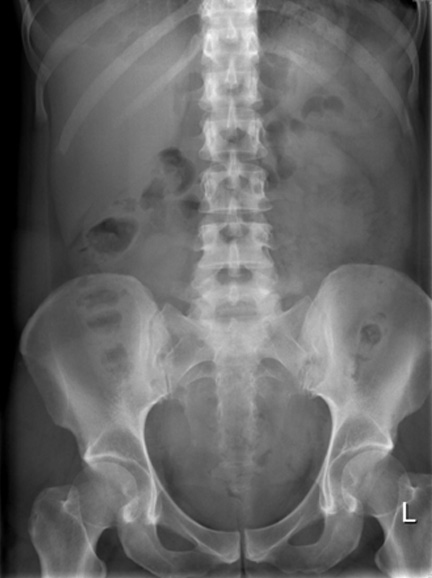

Cliche ASP en face debout : Le

cliche reussite doit etre ananlyse complete

les deux coupoles diapragmatiques en haut et la

sympyse pubienne a inferieure . La penetration ( Kv,

mAs ) soit suffisament pour le plus possible des

differences organes ( reins , foie , deux psoas et

images gazeuse de estom et colon ) |

ASP en face debout : Image

hydro-aerique de la poche gastrique en se voyait sur

1/4 superieure gauche de l'abdomen . A 1/4

inferieure droit de l'abdomen c'est image de gaz

dans colon descadant et ceacum . Lateralement de

l'abdomen c'est deux lame claire de graisseuse de la

paroi de l'abdomen . |